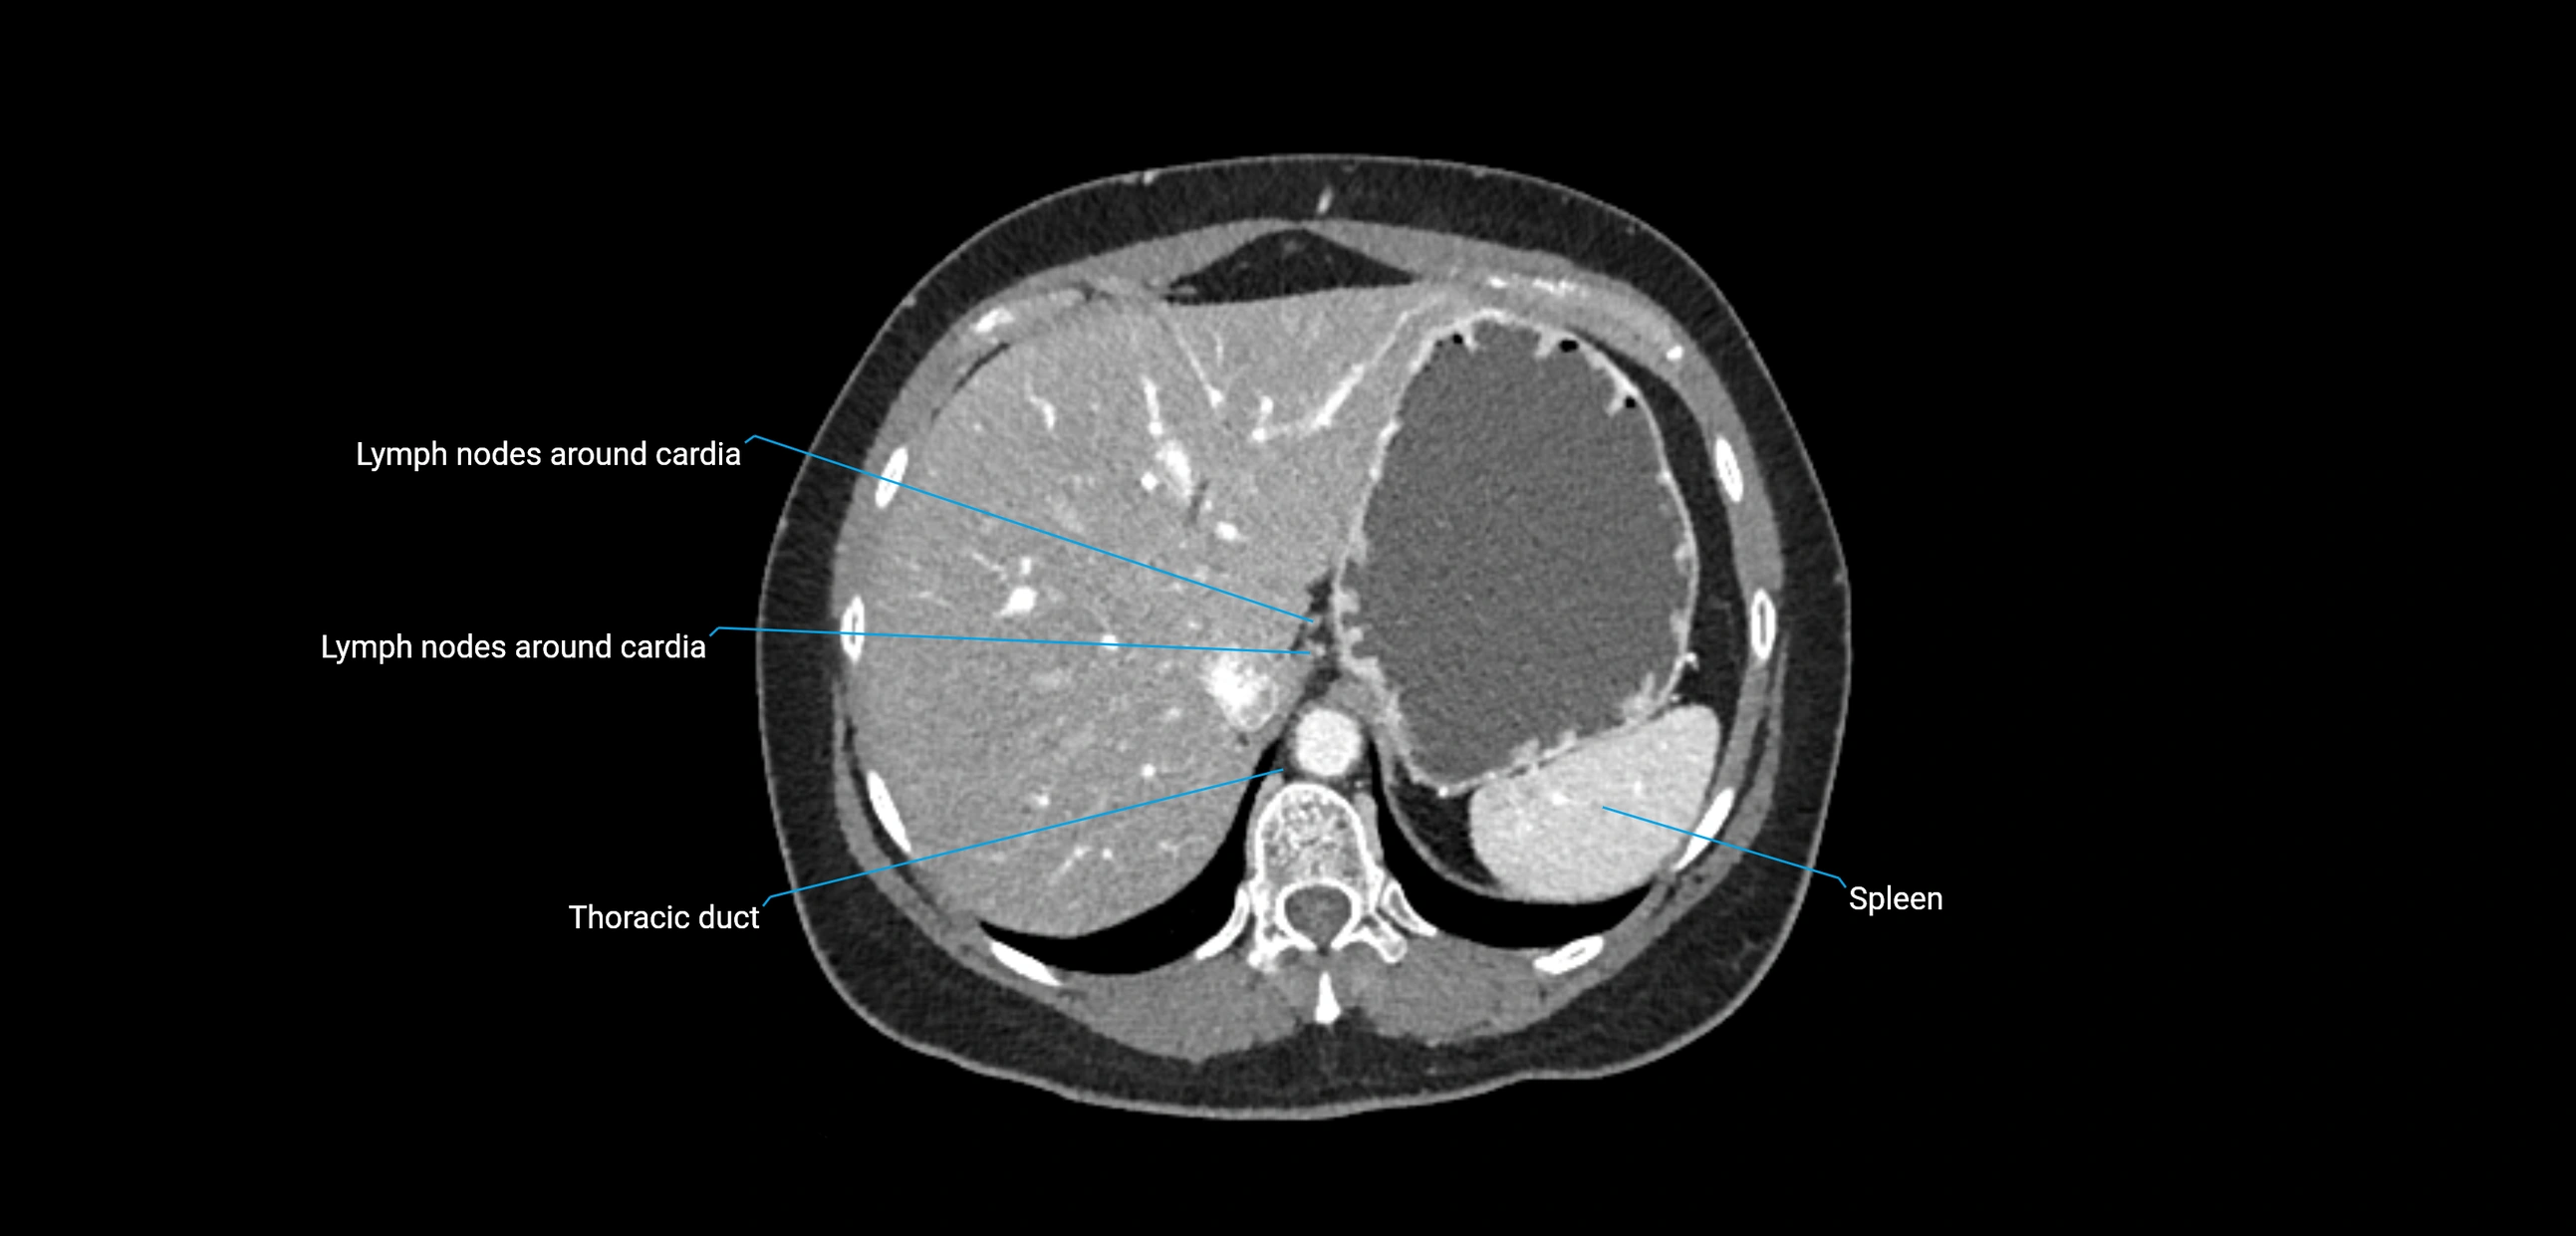

CT image

image